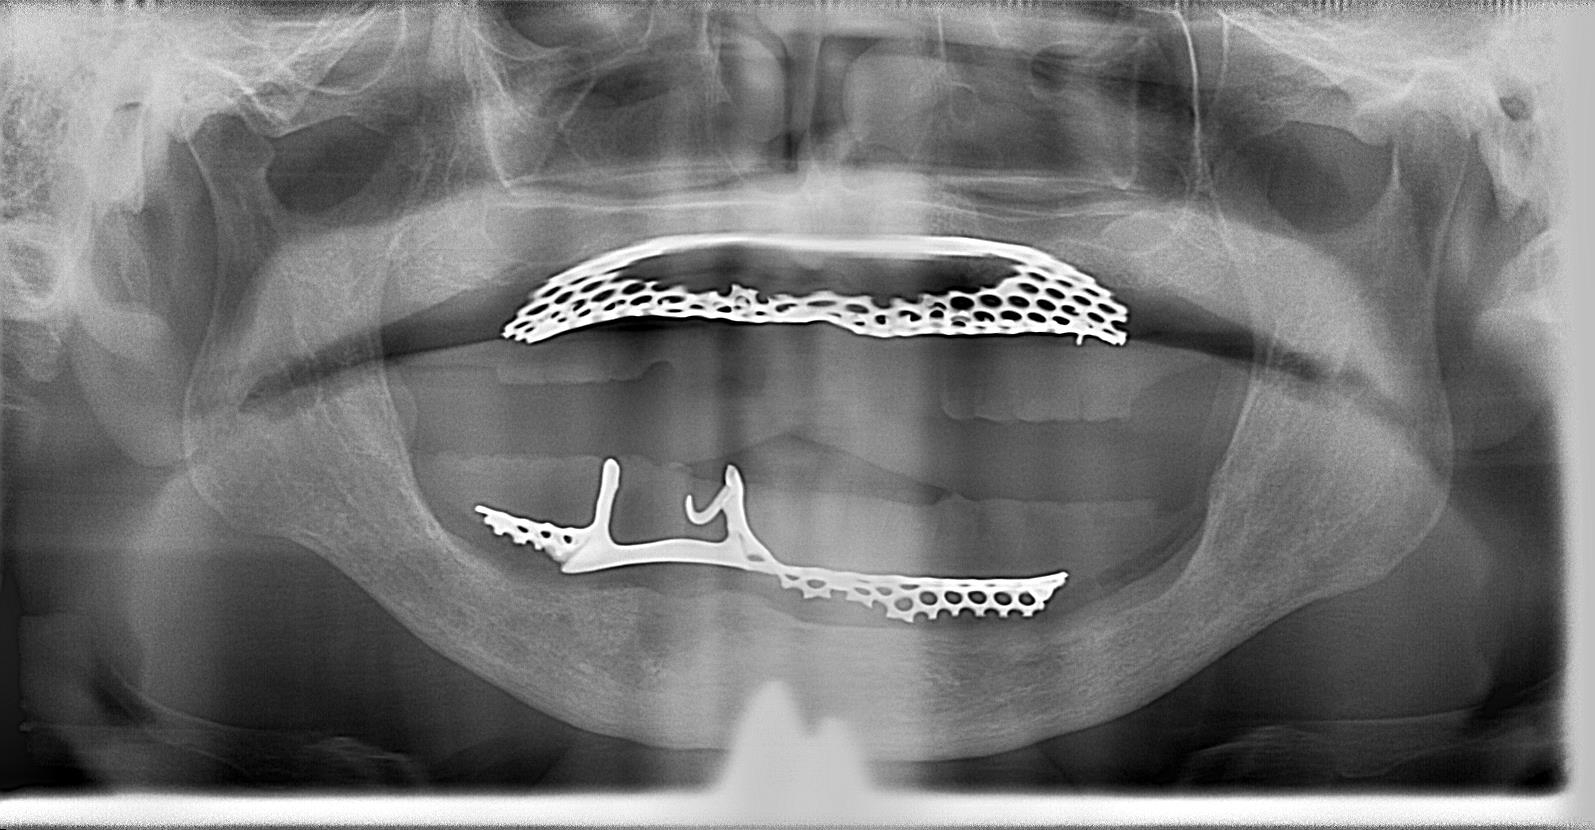

術前の義歯入り パノラマレントゲン写真